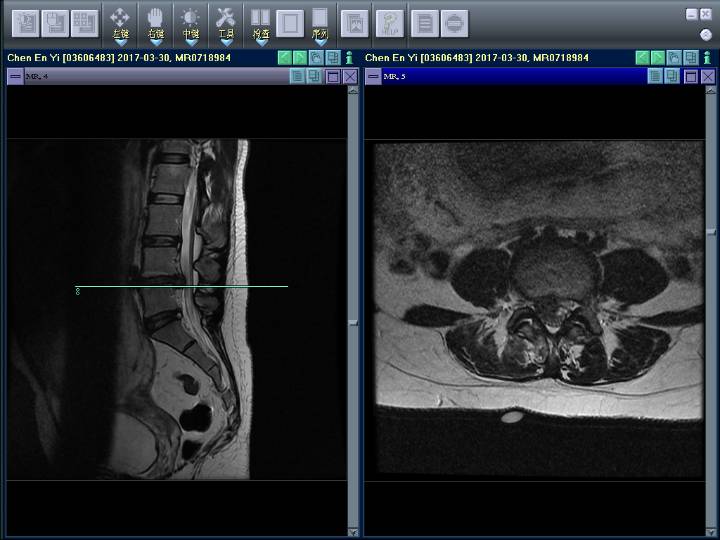

绿线为腰椎间盘突出的地方